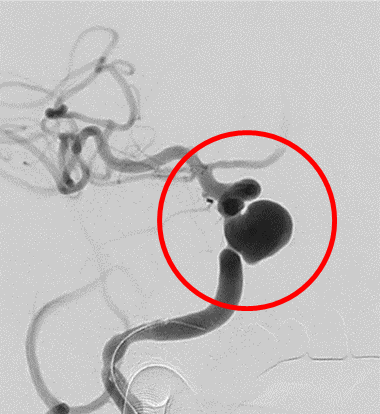

破裂内頚動脈瘤

術前の造影写真です。〇内に脳動脈瘤が造影されています。